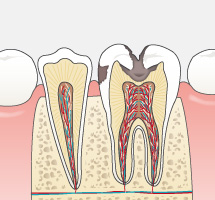

今まで一般的に行われていたむし歯治療は、痛くなったら歯医者に行き治療する、という流れの繰り返しではなかったでしょうか?痛くなってから、むし歯が進行してからの治療は削る・抜歯することが多くなり、徐々に自分自身の天然の歯は「詰め物」や「被せ物」さらには「インプラント」や「入れ歯」になっていきます。天然歯は削ってしまうと二度と元には戻りません。

可能な限りご自身の歯で食事を楽しんだり、話したりして健康な生活を送っていただきたい。だからこそ当院ではできるだけ歯を残す治療をおこないます。単なる対症療法の“削って詰める”ではなく、病原菌の除去をしてからMI(Minimal Intervention:できるかぎり削らず、削っても最小の範囲で)の考えのもと原因療法を施し、治療後はむし歯の再発や新たなむし歯の発生を予防することを目標としています。